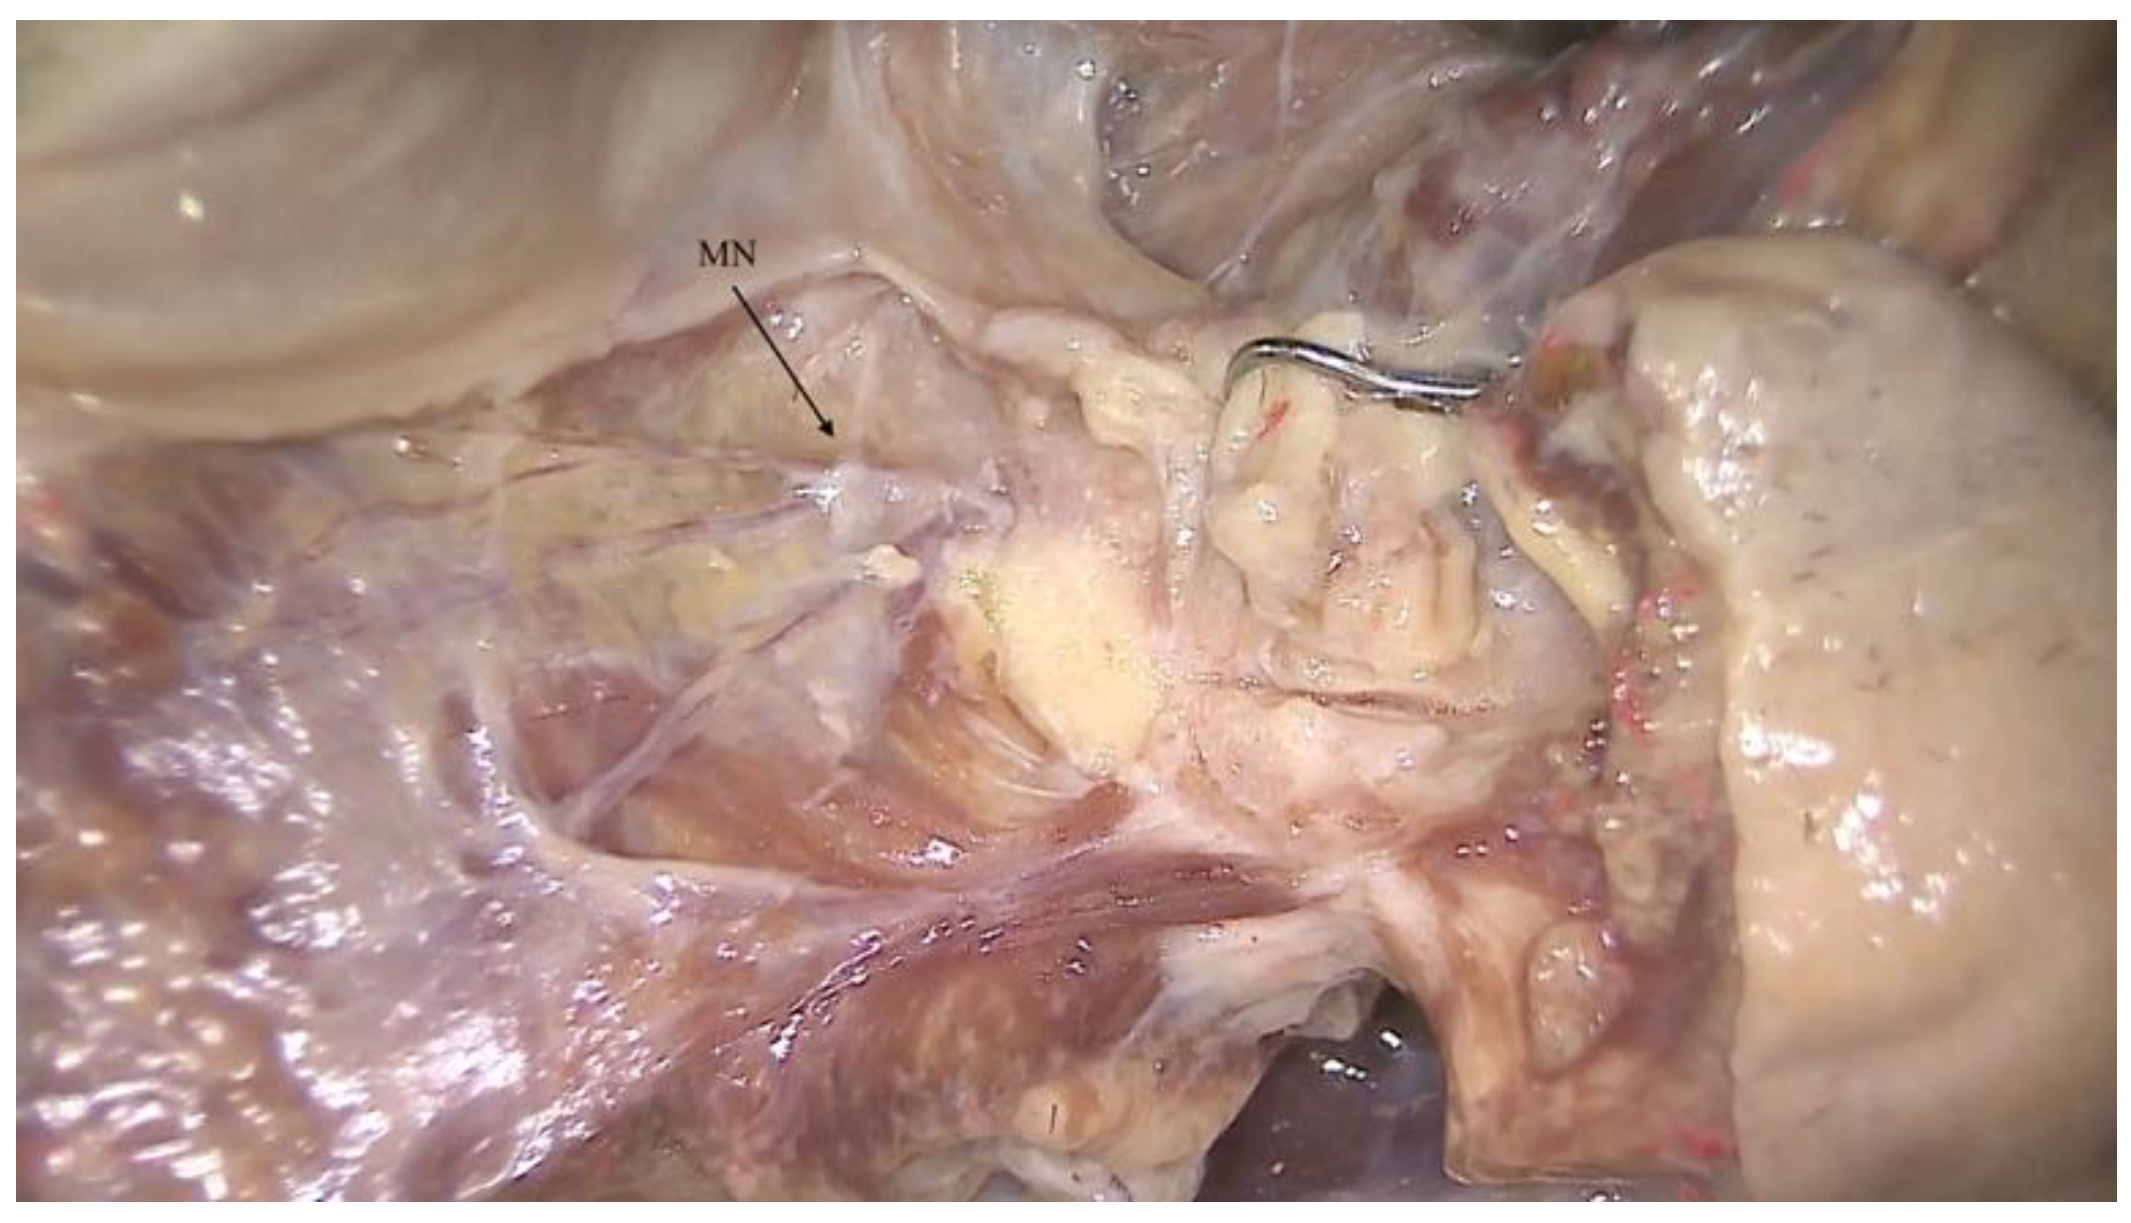

Figure 1. Anatomical pictures of a human body dissection showing the mental nerve fiber (MN), which is a common target of anesthesia before performing surgery in the mandibular symphysis.

2. Materials and Methods